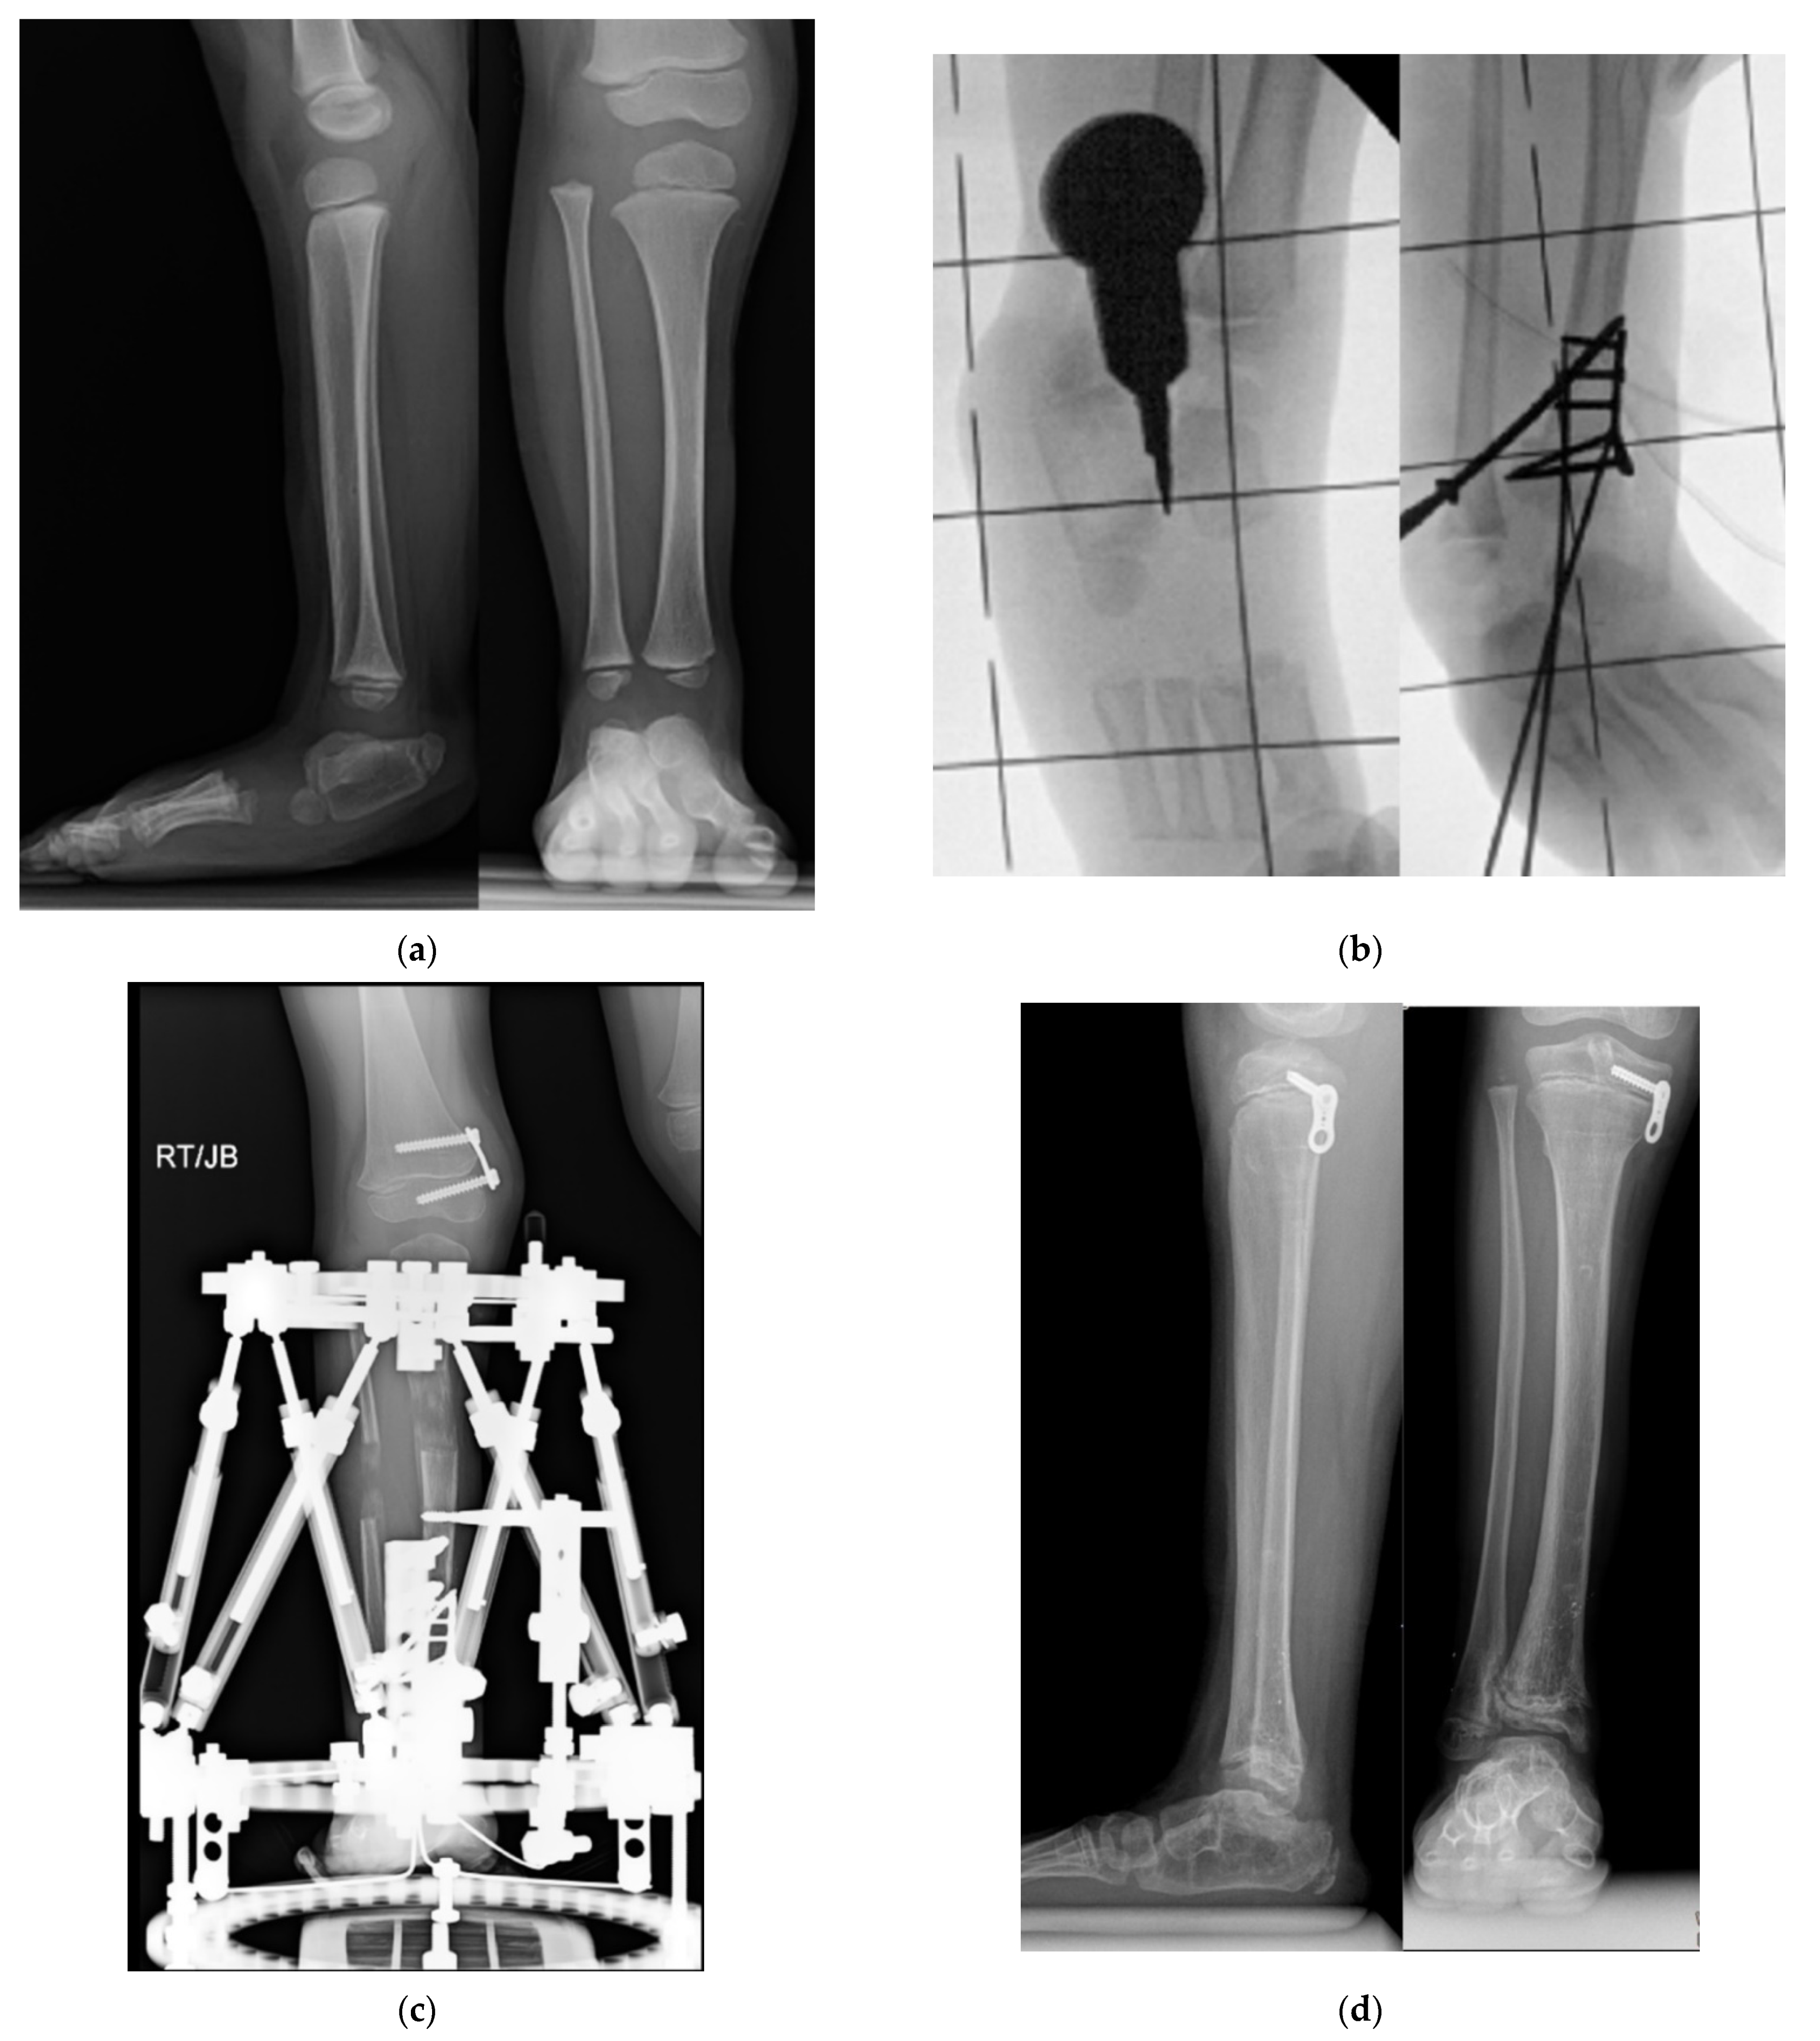

Figure 3.

A three-dimensional CT scan of distal tibia and foot (left Anteroposterior (AP) view, middle lateral view and right posteroanterior (PA) views) in a 13-year-old boy with untreated type 3c fibular hemimelia with fixed equino-valgus of the hindfoot. Despite the presence of a fibula, there is valgus-procurvatum malorientation of the ankle plafond, and a malunited subtalar coalition. The calcaneus is articulating with the fibula. There are also calcaneo-cuboid and talo-navicular coalitions with midfoot adductus.